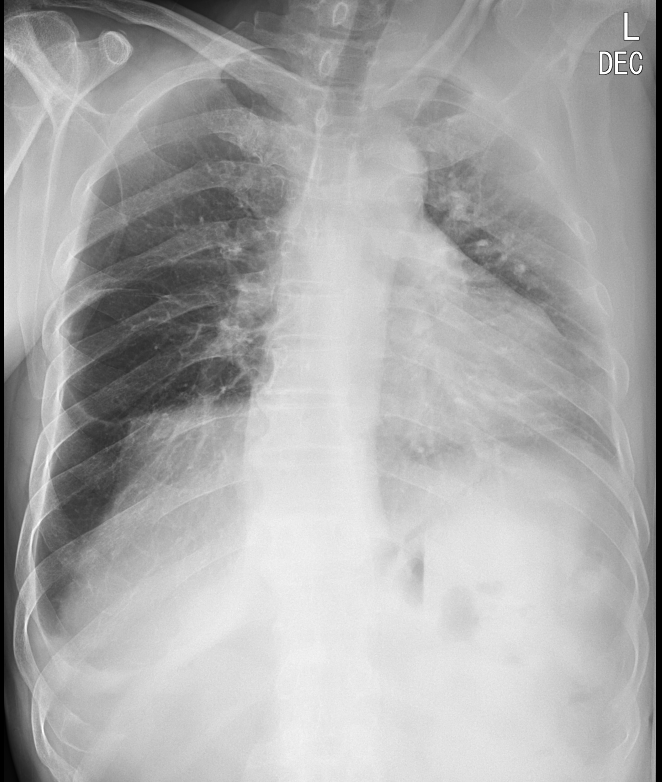

2. decubitus view ; 옆으로 누워 촬영하는 흉부 x ray

옆구리를 바닥에 대고 누워서 촬영한 영상은 다음과 같은 사진을 보여준다.

바로 pleural effusion(흉수)가 있거나 의심되는 상황에서 촬영하게 된다. 물병에 물을 담고 병을 세우거나 눕힐 때면 물은 중력에 의해 바닥에 깔리게 된다. 마찬가지로 흉수는 흉강안쪽에 차는 물이기 때문에 서있는 자세에서는 흉강의 가장 아래쪽 갈비뼈와 diaphragm이 만나는 위치인 CPA(costophrenic angle) 쪽으로 물이차게 된다. 따라서 chest PA에서는 해당 부분이 예리하지 않게 blunting 되는 모습을 보인다면 흉수를 의심할 수 있다. 양이 적을 경우엔 애매한 소견이 나타날 수 있는데, 이런 경우 decubitus view를 촬영하게 되면 흉수가 있는지 없는지 알 수 있게 된다.

위 사진을 예시로 보면 Chest PA로는 환자의 우측 흉강에만 흉수가 보인다. decubitus view를 촬영해 보면 우측으로는 흉수가 많이 보이고, 좌측은 적지만 흉수가 있어 보임을 알 수 있다.